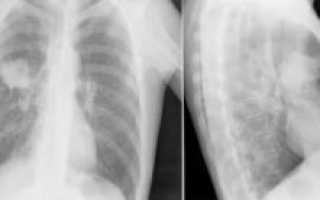

Более высокая результативность наблюдается при создании снимка в двух проекциях: каждый из них покажет тени легких в разных ракурсах, то есть позволит увидеть патологические очаги, которые не были видны с другой позиции.

Выглядит рак на рентгеновском снимке как затемненное пятно. Внешний вид злокачественных опухолей может быть различным в зависимости от формы заболевания, стадии ее развития и других факторов. Составляя описание, врач обращает внимание на локализацию теней. По этому признаку заболевание определяется как центральный или периферический, перибронхиальный или бронхоальвеолярный тип.

По локализации периферический рак легкого значительно отличается от центрального. Очаг поражения тканей располагается на поверхности органа, поэтому проявляется четче. Внешний вид такого типа рака легкого на рентгене стандартный — темная тень с признаками распада тканей.

Видимость метастазов в легких на рентгене достаточно хорошая. В отличие от первичных опухолей, такие новообразования всегда множественные. По внешнему виду затемнения характеризуются как негомогенные структуры на поверхности или в толще органов, с нечетким краем и неправильной формой.

При прогрессировании метастатического процесса рентгеновский снимок легких при раке обнаруживает распространенное поражение тканей, схожее с диссеминированной формой туберкулеза — пятна могут сливаться, образуя обширные затемнения. На последних стадиях на снимках становятся видны некротические очаги с распадающимися тканями, полости, наполненные экссудатом.

Если у врача есть подозрение на скрытую дополнительными тенями опухоль, рекомендовано проведение рентгена в нескольких проекциях. Если на снимках в фронтальной позиции тень ребер и сердца мешает визуализировать рак, в боковой или наклонной врач сможет верно интерпретировать природу тени.